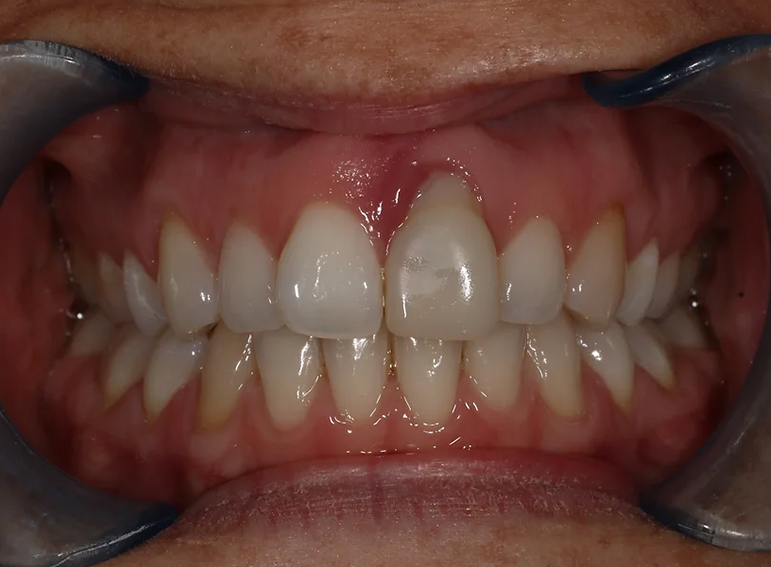

External cervical resorption extracted with a temporary adhesive bridge and final adhesive bridge.